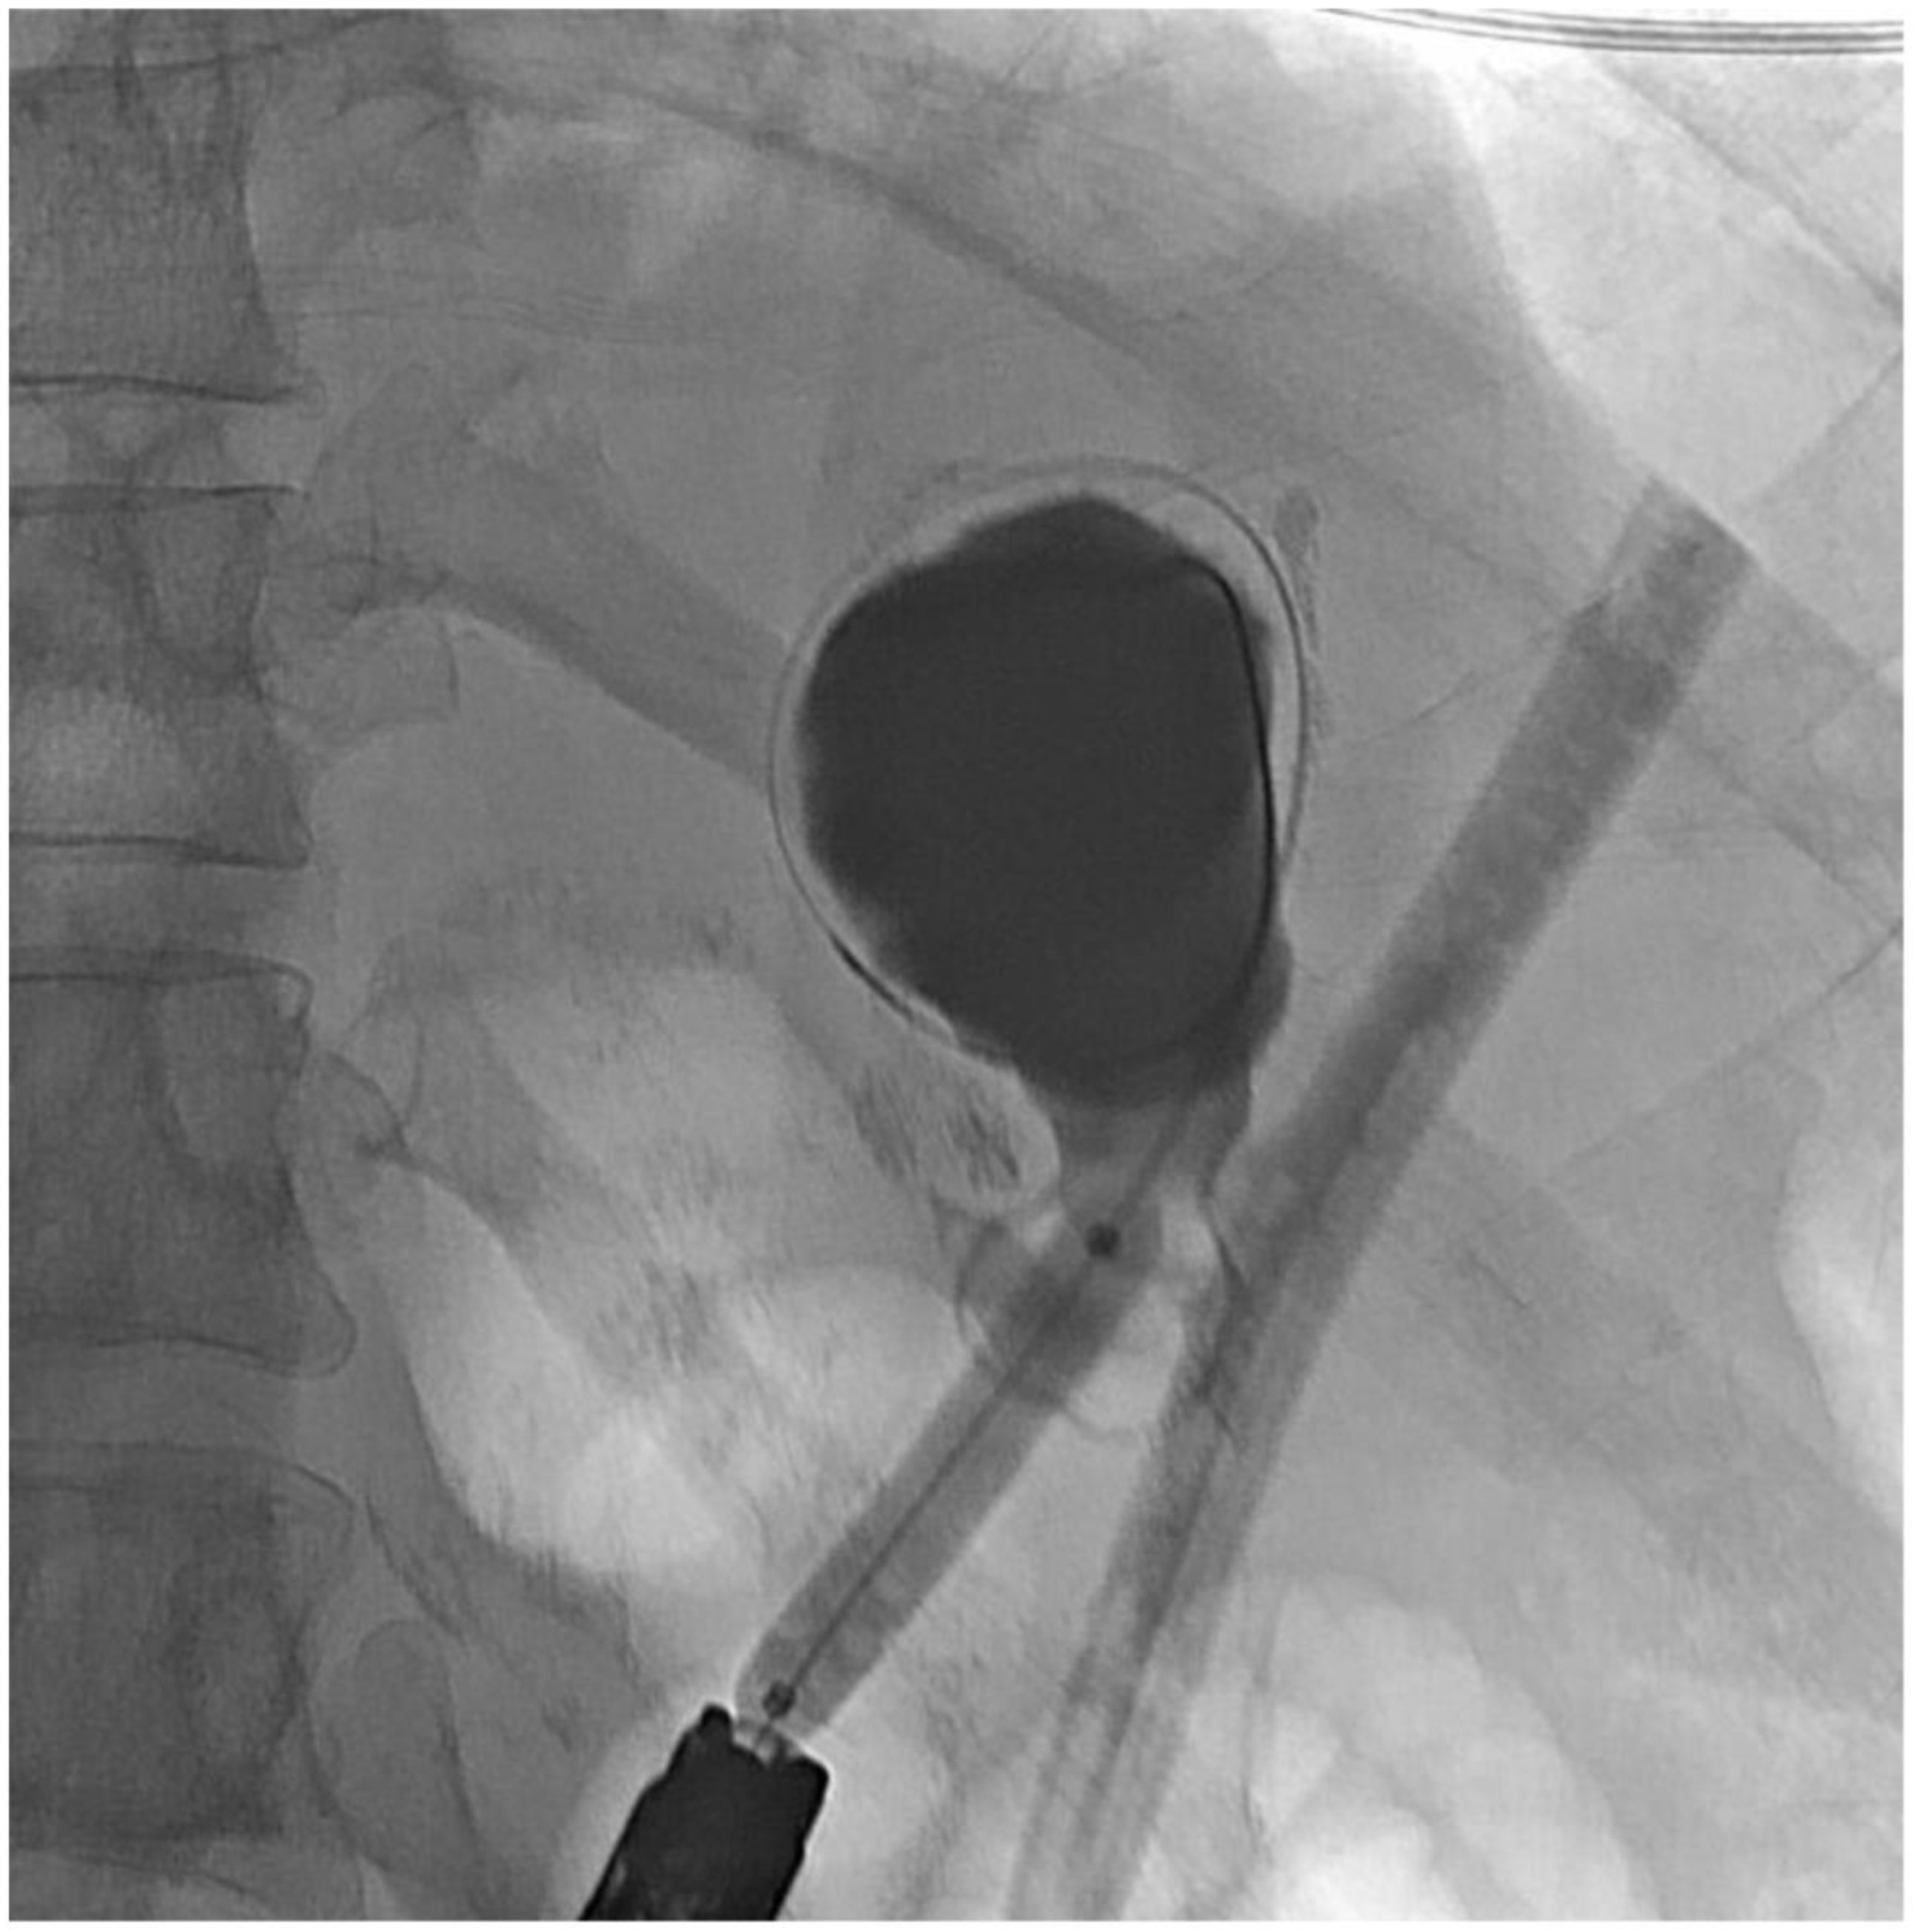

2. Detailed Case Description